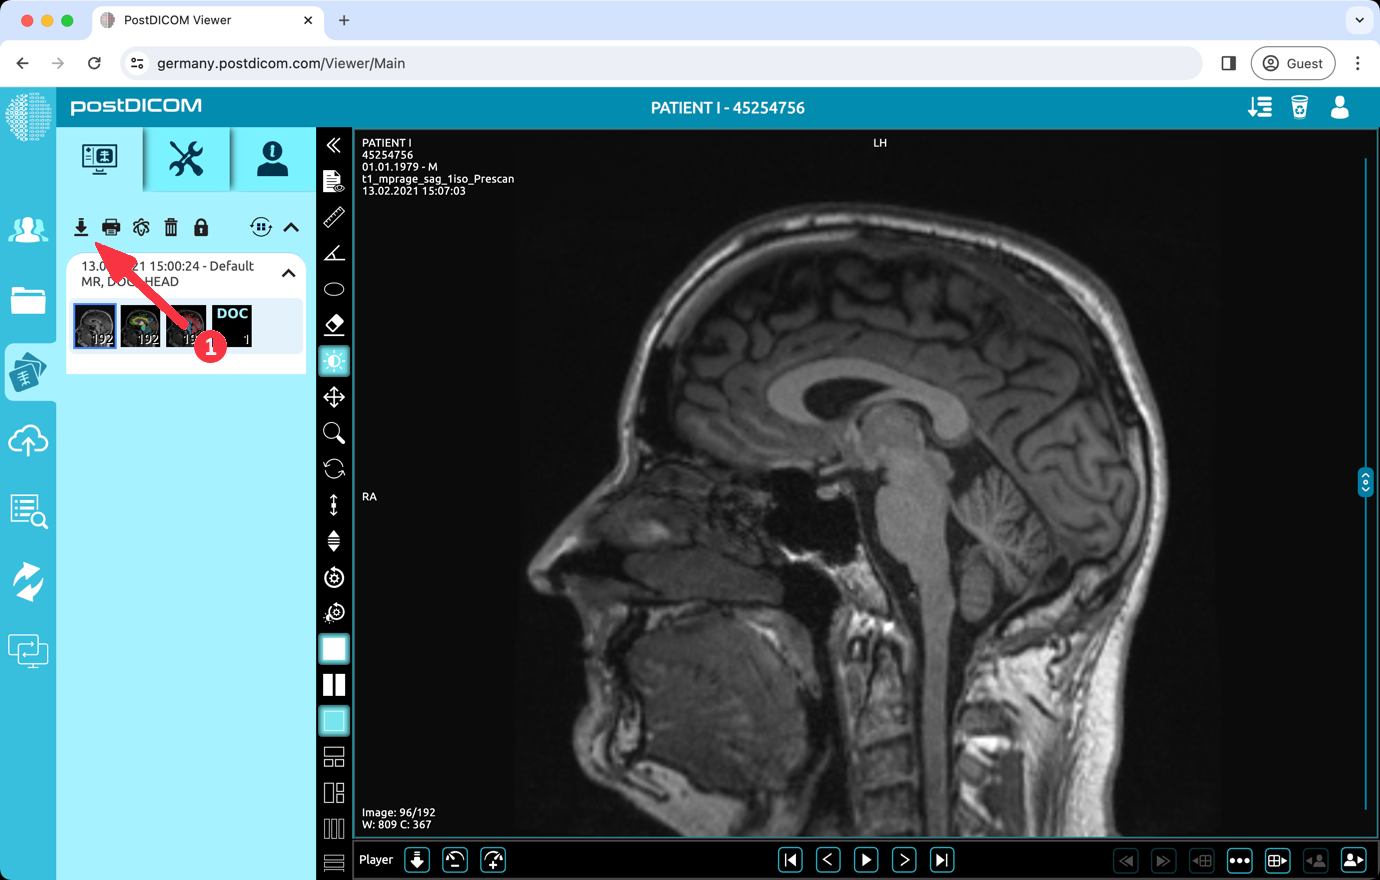

To download images with CD Viewer, open the patient study that you want to download.

Click the 'Download' button which is top left on the screen.